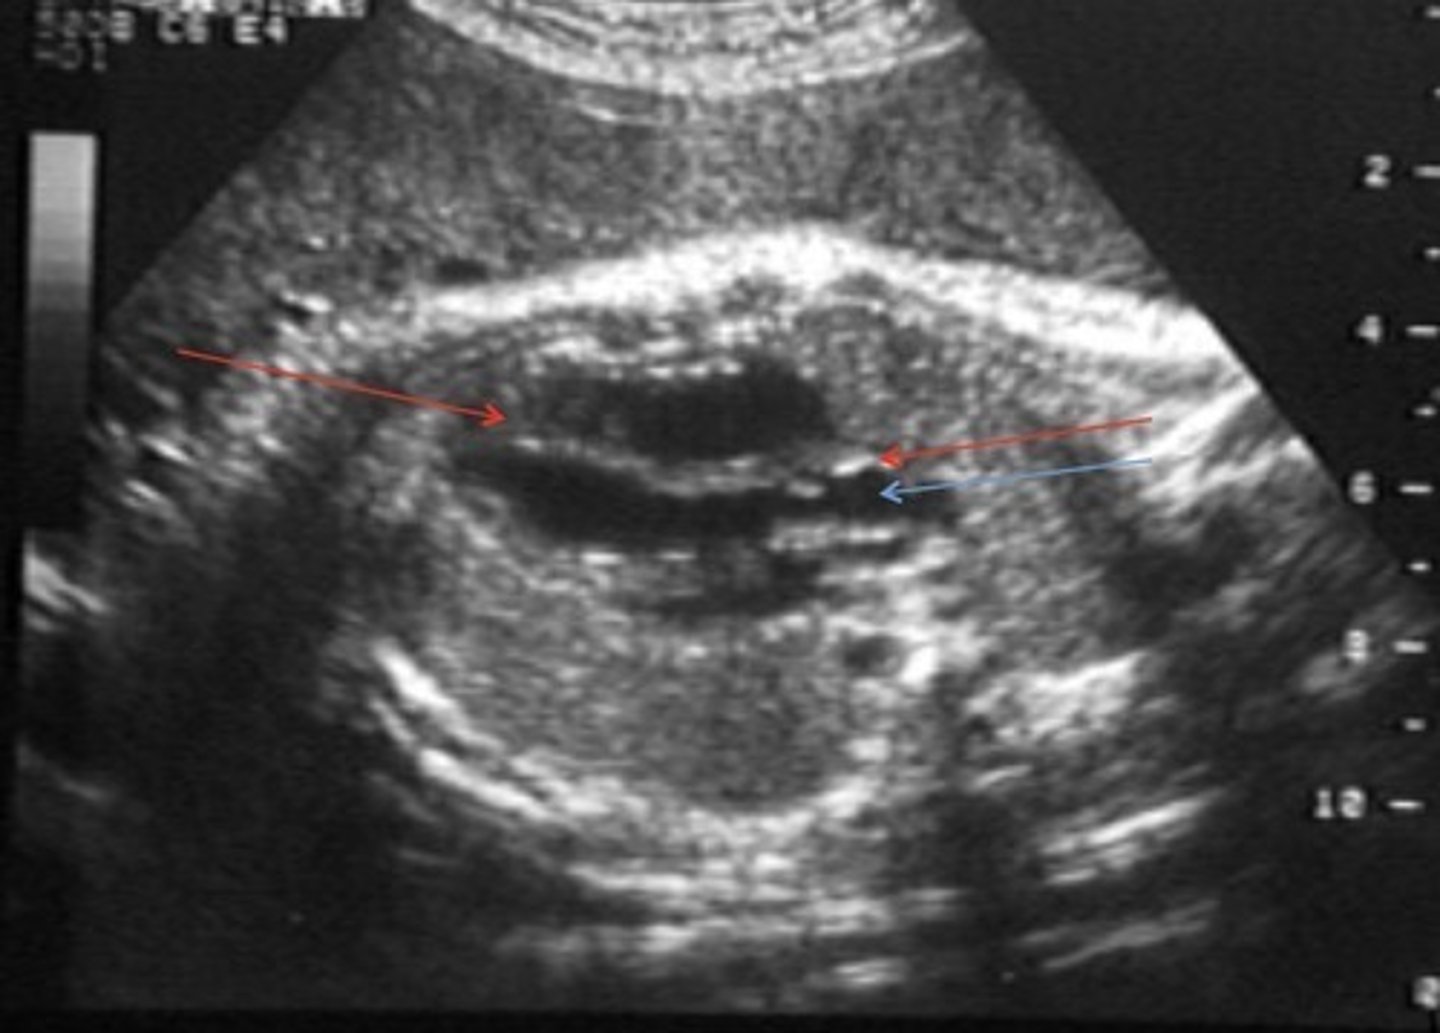

Grade 0 Hydronephrosis

Normal kidney

Grade 1 Hydronephrosis - Pyelectasis

Fluid within renal pelvis, but small enough to be considered insignificant/within normal range

Grade 2 Hydronephrosis

Pelvis is > 10 mm

Few calyces seen

Cortex is normal